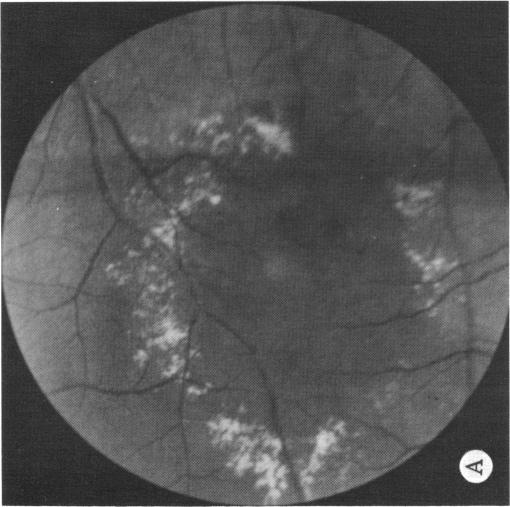

Coats' disease and congenital vascular retinopathy.

Trans Am Ophthalmol Soc. 1976;74:365-424.